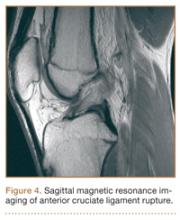

Although snowboarders’ lower extremity injuries are primarily ankle injuries, snowboarders are also at risk for serious knee issues when landing from jumps. In skiers, anterior cruciate ligament (ACL) injuries have 5 well-established mechanisms, all involving separation of the feet and a twisting force in the knee (Figures 4, 5): boot-induced anterior drawer mechanism, phantom-foot mechanism, valgus-external rotation, forceful quadriceps muscle contraction, and a combination of internal rotation and extension.8,12 A valgus–external rotation mechanism of knee injury occurs when external rotation of the tibia results from the skier catching the inside edge of the front of the ski. A valgus force acts on the knee as the lower leg is abducted during forward momentum. The torque created on the knee joint is amplified by the length of the knee and commonly results in an ACL injury or medial collateral ligament injury.6 Reports indicate that the phantom-foot mechanism is the most common mechanism of ACL injury among skiers.6,13,14 In this situation, internal rotation of the knee results when an off-balance skier falls backward, which causes the knee to hyperflex. The skier catches an inside edge on the snow, which creates a torque that rotates the tibia relative to the femur and results in injury to the ACL.6,14 A boot-induced anterior drawer mechanism occurs during a landing, when the tail of the ski lands first and in an off-balance position, resulting in a load transmitted through the skis to the skier; this load causes an anterior drawer of the ski boot and tibia relative to the femur, straining the ACL and causing ACL rupture.6,13,14 In the forceful quadriceps muscle contraction mechanism of ACL injury, a forceful quadriceps contraction occurs after a jump to prevent a backward fall. With the knee in flexion, this quadriceps contraction causes an anterior translation of the tibia, resulting in ACL rupture.13,14